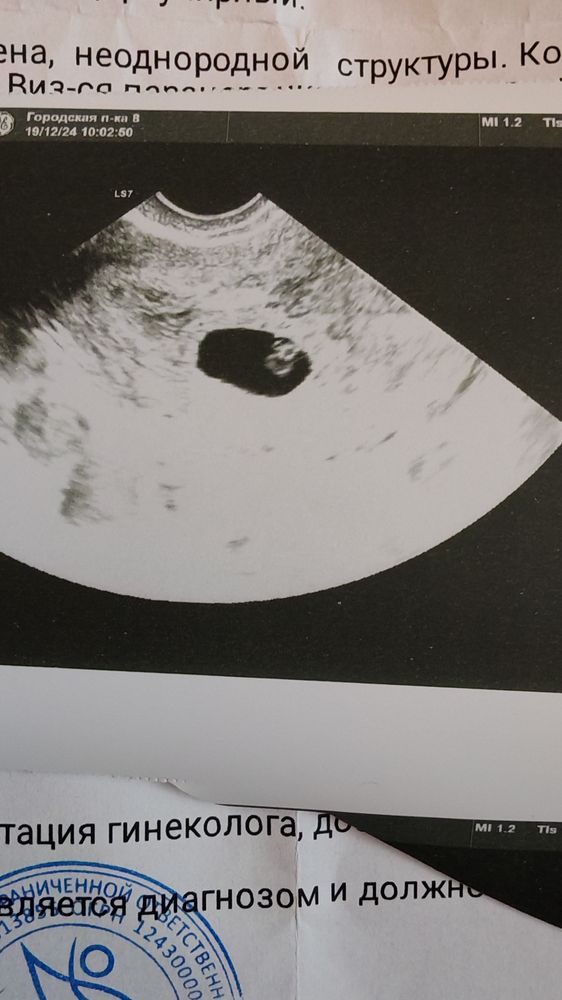

Ирина, у меня тесты на овуляцию были положительные 31и1 числа , возможно овуляция была 2..это самое позднее , тесты были положительные на 11дпо. 19 ноября узи показало плодное яйцо 3мм, 26 ноября 7,1 мм, эмбриона не увидели был желтый мешок , сказала что на нем формируется эмбрион и через пару дней будет видно кольцо с бриллиантом.. Больше я не ходила на узи пошла в жк . вот от жк сегодня прошла узи , и прошла еще платно сейчас, даже еще меньше увидели ктр (.

Изображениедаже не видно ничего (

Может у вас двойная овуляция была? про желтое тело не увидела в заключении. У меня такие параметры по узи в 7 недель были но у меня эко и все четко по срокам, подождите недельку.

Ирина, жт было одно с правой стороны с самого начала овуляции больше не было , в вас эмбриональный срок стоял 7нелель ? Я уже ничего не понимаю просто от овуляции если считать то у меня 7 недель , даже если тесты не так показали максимум она могла быть 2 числа это 6 недель и 5 дней. Эмбриональный был бы

Ирина, понятно, у меня получается тогда минимум 47 .. Пипец 🤦‍♀️

Нина, нет сказали рано ещё , переделала платно узи одно и тоже , самое мне не понятное , что я дуиала что мне поставили эмбриональный срок , а оказывается по всем таблицам акушерский ..